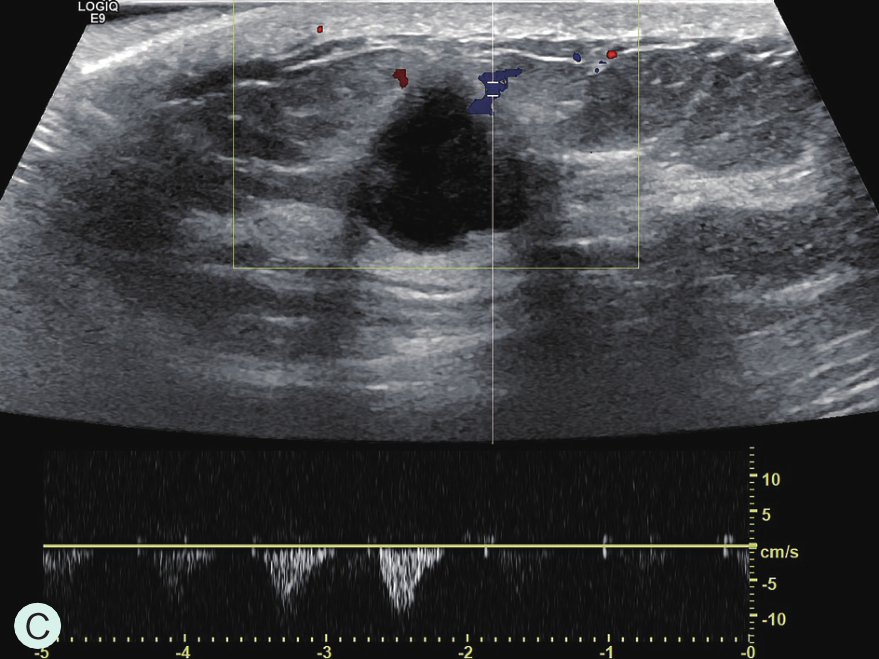

图2-2-1 确定造影病灶

A.病灶二维图像;B、C.病灶CDFI图像;D.同侧腋窝淋巴结情况;E.病灶弹性成像图像